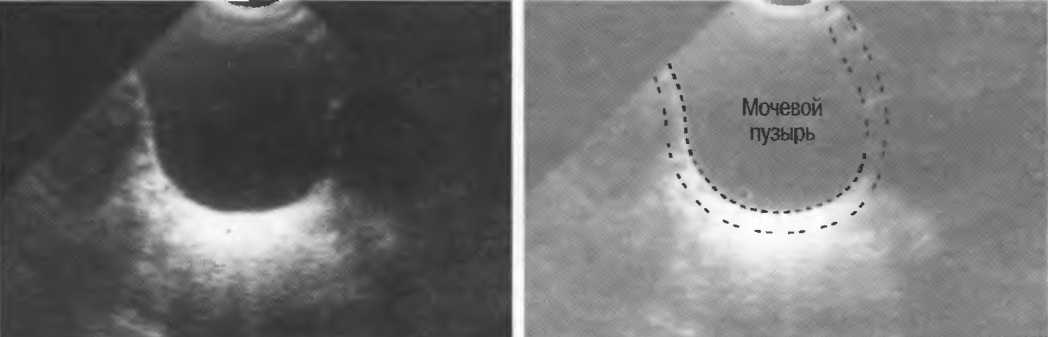

Акустическое окно |

Ткань или структура, не препятствующая распространению ультразвуковых волн и таким образом являющаяся окном для визуализации более глубоко расположенных структур. Например, заполненный жидкостью мочевой пузырь создает великолепное акустическое окно, через которое происходит визуализация тазовых структур. Обычно правую почку легче визуализировать через печень, чем через толстые мышцы спины. В этом случае печень является акустическим окном. |

Реверберация |

Отражение ультразвуковых волн назад и вперед между двумя сильно отражающими поверхностями, параллельными или почти параллельными. В этом случае происходит задержка возвращения отраженного сигнала к датчику, в результате чего изображения отражающих поверхностей расположены глубже, чем они есть на самом деле. Это также может проявляться в удвоении или утроении изображения. Например, реверберации могут наблюдаться в передних отделах перерастянутого мочевого пузыря или между параллельными мышцами стенки брюшной полости. |

Акустическое усиление и акустическая тень

Чистые жидкости проводят ультразвуковой сигнал без существенного ослабления, поэтому отраженные эхосигналы, идущие от тканей, расположенных за жидкостью, обычно усилены (более яркие). Этот феномен известен как «акустическое усиление» (рис. 10а). Прием достаточного количества жидкости для заполнения желудка дает смещение кишечника, содержащего газ, и тем самым создает акустическое окно. Это особенно полезно для визуализации тела и хвоста поджелудочной железы.

Газ в кишечнике или еще где-либо вызывает появление различных эхографических феноменов. Ультразвуковой луч может рассеиваться, отражаться, поглощаться и преломляться таким образом, что становится практически невозможной визуализация подлежащих структур. По этой причине ультразвук не может быть использован для визуализации нормальных легких или выявления заболевания легких, за исключением объемных процессов, расположенных по периферии органа. Рентгенография грудной клетки в этом случае даст большую информацию.

Плотные материалы, такие как кости или камни, дают акустическую тень на структуры, расположенные сзади, в результате того что ультразвуковая волна не проходит через них. Этот феномен получил название «акустической тени». Например, ребра могут экранировать ультразвуковой поток, поэтому структуры, расположенные за ними, нужно исследовать в косом направлении по межреберным промежуткам (рис. 10б,в).